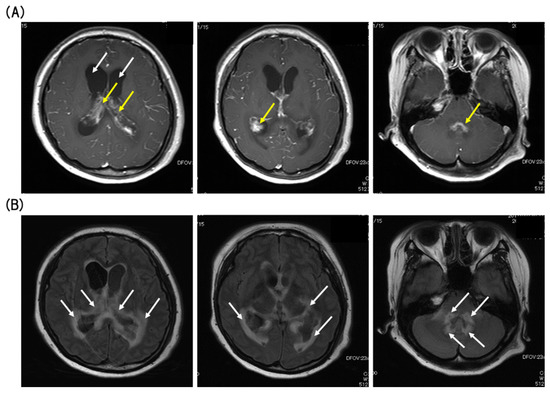

On day 230 after transplantation, she suddenly arrived at the emergency room of our hospital presenting with severe headache, nausea, and vomiting without B symptoms (fever, night sweats, and body weight loss). Gadolinium-enhanced magnetic resonance imaging (MRI) studies of the brain demonstrated lesions in both lateral ventricles with heterogeneous enhancement, on which the lesions appeared to arise from the choroid plexus. Bilateral ventricles were dilated, and the margins of the ventricles were enhanced by contrast-enhanced fluid-attenuated inversion recovery (FLAIR)-MRI (Figure 2).

Clinical features of patients with choroid plexus lymphoma are nonspecific, and thus, MRI images play a crucial role in the disease diagnosis and are essential for monitoring the response to treatment. In most cases, primary choroid plexus lymphomas are observed as enhanced mass lesions on MRI scans without hydrocephalus [17,21]. Because hydrocephalus and the margins of the ventricles were enhanced by FLAIR-MRI in the presented case, we could not rule out the possibility that the lesions were related to various types of infections. Therefore, the final diagnosis was made by the surgical biopsy.

Figure 2. (A) T1-weighted (T1W) axial gadolinium-enhanced magnetic resonance imaging (MRI) showed Bilateral ventricle enlargement (white arrows), and hypertrophy choroid plexus (yellow arrows) with heterogeneous enhancement (axial sections). (B) Fluid-attenuated inversion recovery image (FLAIR) revealed high-intensity periventricular white-matter changes (white arrows) (axial sections).